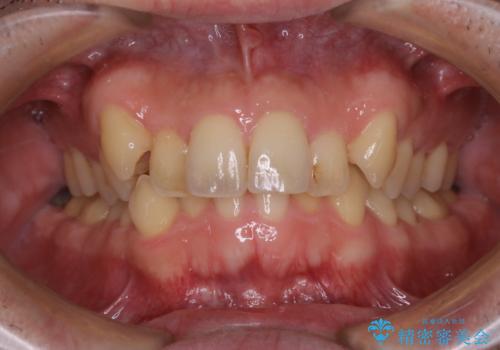

タバコのヤニをPMTCできれいに

- タバコによる着色が気になるため、全て取りたいとのことで来院されました。PMTC60分コースを行いました。

タバコに含まれているものの中で、タールというものが歯の着色の原因です。その、タールによって付着してしまった着色はご自身で落とすことはできません。

PMTCは、歯に付着した汚れを除去していくため、着色が気になる場合にも行うことができます。ご自身でのセルフケアだけで着色を落とそうとすると、逆に歯を傷つけてしまったり、精密に汚れを除去できないこともあります。また、日常生活で着色しやすい飲食物を避けたりすることはストレスに感じてしまったり、あまり現実的ではありません。